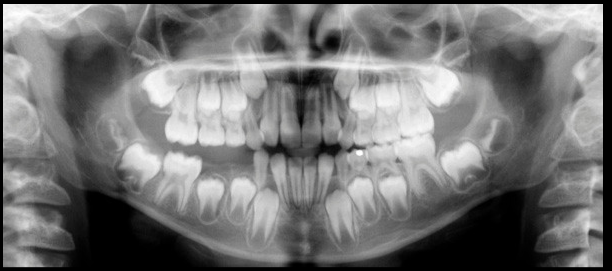

Paciente masculino 8 años de edad, es referido a la consulta para la evaluación con tomografía volumétrica por presentar un aumento de volumen indurado en la zona molar inferior derecha. En la radiografía panorámica notamos la ausencia de la piezas 8.4, 8.5 y la pieza 4.6 en infraoclusión. Se realiza estudio con tomografía volumétrica (Picasso E-WOO), se grafican cortes axiales, coronales y transaxiales que muestran a nivel de la pieza 4.6 ensanchamiento del espacio pericoronario hacia vestibular y reacción periostal que se extiende hacia la pieza 4.5 y 4.7.